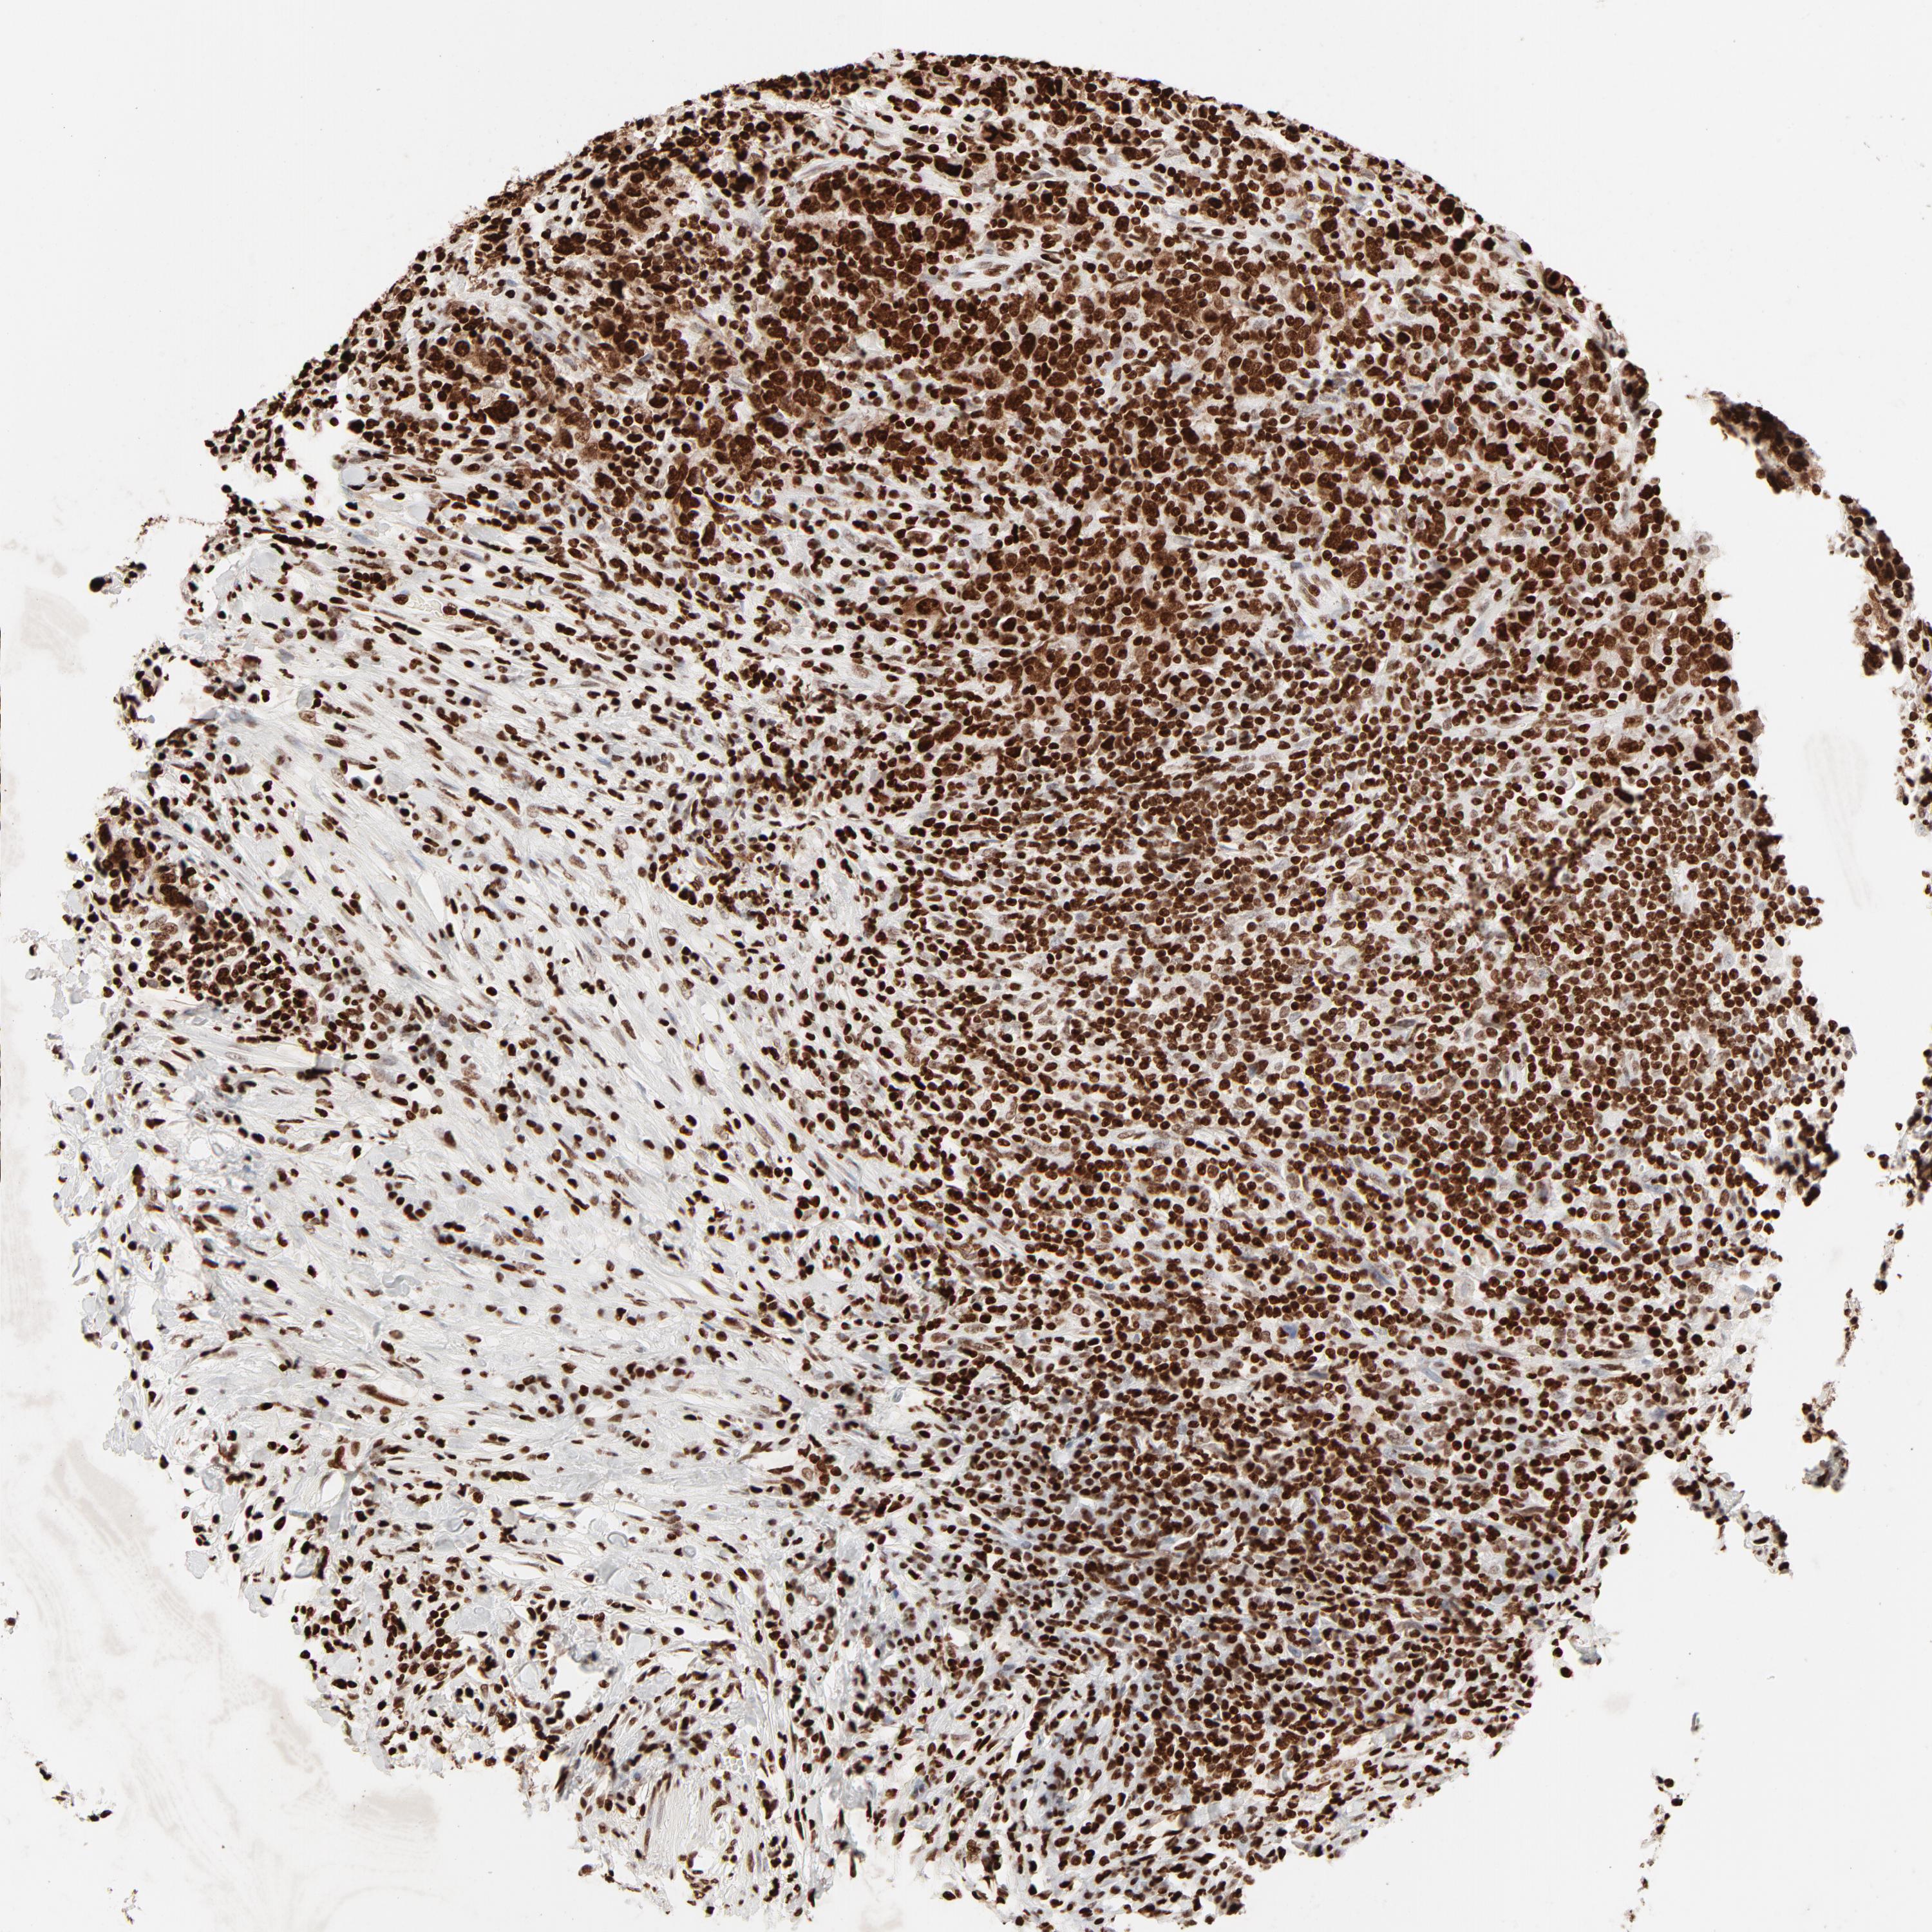

UROTHELIAL CANCER - Protein expressioni

A mouse-over function shows sample information and annotation data. Click on an image to view it in a full screen mode. Samples can be filtered based on level of antibody staining by selecting one or several of the following categories: high, medium, low and not detected. The assay and annotation is described here.

Antibody stainingi

Antibody staining in the annotated cell types in the current human tissue is reported as not detected, low, medium, or high, based on conventional immunohistochemistry profiling in selected tissues. This score is based on the combination of the staining intensity and fraction of stained cells.

Each image is clickable and will lead to virtual microscopy that enables deeper exploration of all samples and also displays staining intensity scores, fraction scores and subcellular localization as well as patient and tissue information for each sample.

Antibody HPA003506

Antibody CAB005873

Urothelial carcinoma, High grade

Urothelial carcinoma, Low grade